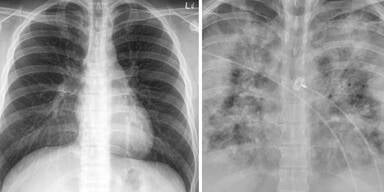

Wie groß der Unterschied punkto Lungenschäden zwischen Corona-Geimpften und Ungeimpften sein kann, zeigen zwei Röntgenbilder.

Wie groß der Unterschied punkto Lungenschäden zwischen Geimpften und Ungeimpften sein kann, zeigen zwei Röntgenbilder:

With Without

Vaccination Vaccination pic.twitter.com/GIcb5mJQz9

Auf den Röntgenaufnahmen, die Faheem Younus, Leiter der Abteilung "Infectious Diseases" an der University of Maryland, auf Twitter geteilt hat, sieht man zwei Lungen, die sich deutlich unterscheiden. In beiden Fällen stammen die Bilder von einem Covid-19-Patienten. Auf der einen Aufnahme sind deutlich mehr helle Schatten zu sehen als auf der anderen. Das Röntgenbild zeigt die Lunge einer ungeimpften Person. Bei den weissen Schatten handelt es sich um sogenannte Milchglastrübungen, welche entstehen bei Entzündungen der Lunge.

Anfang des Jahres, schlug auch die Ärztin, Brittany Bankhead-Kendall, Alarm: "Nach einer überstandenen Covid-Erkrankung sehen Lungen schlimmer aus als jede Raucherlunge, die wir je gesehen haben."

Es zeigen sich dramatischen Unterschiede zwischen einer gesunden Lunge und einer Post-Covid-Lunge.